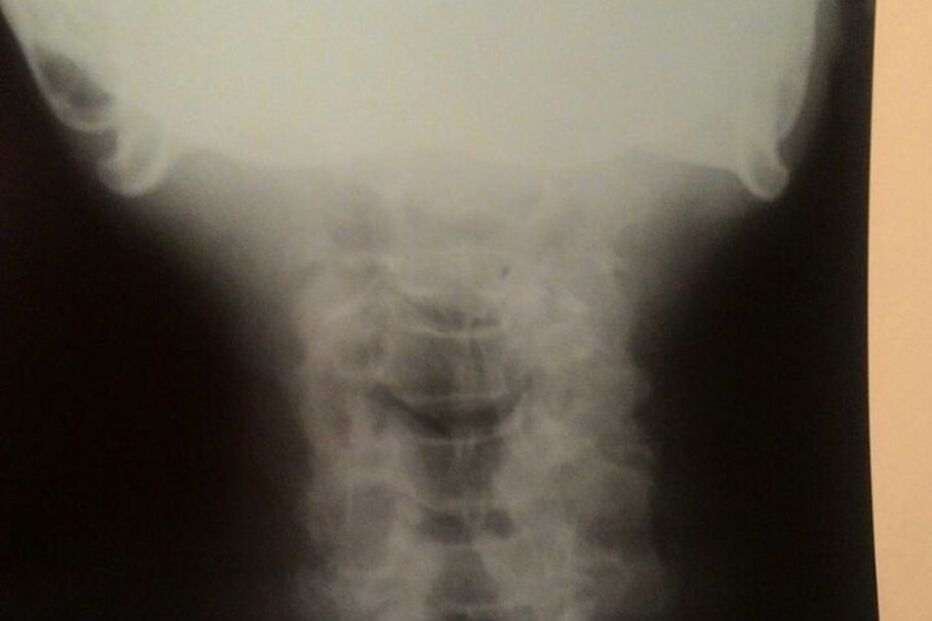

Segundo o site G1, que falou com a filha de Antonio, foi feito um raio-X para verificar que a dentadura estava presa. Foi dito à família que era preciso um aparelho de endoscopia para verificar a situação e de que forma seria possível retirar a prótese. No entanto o hospital não dispunha do aparelho há vários dias.